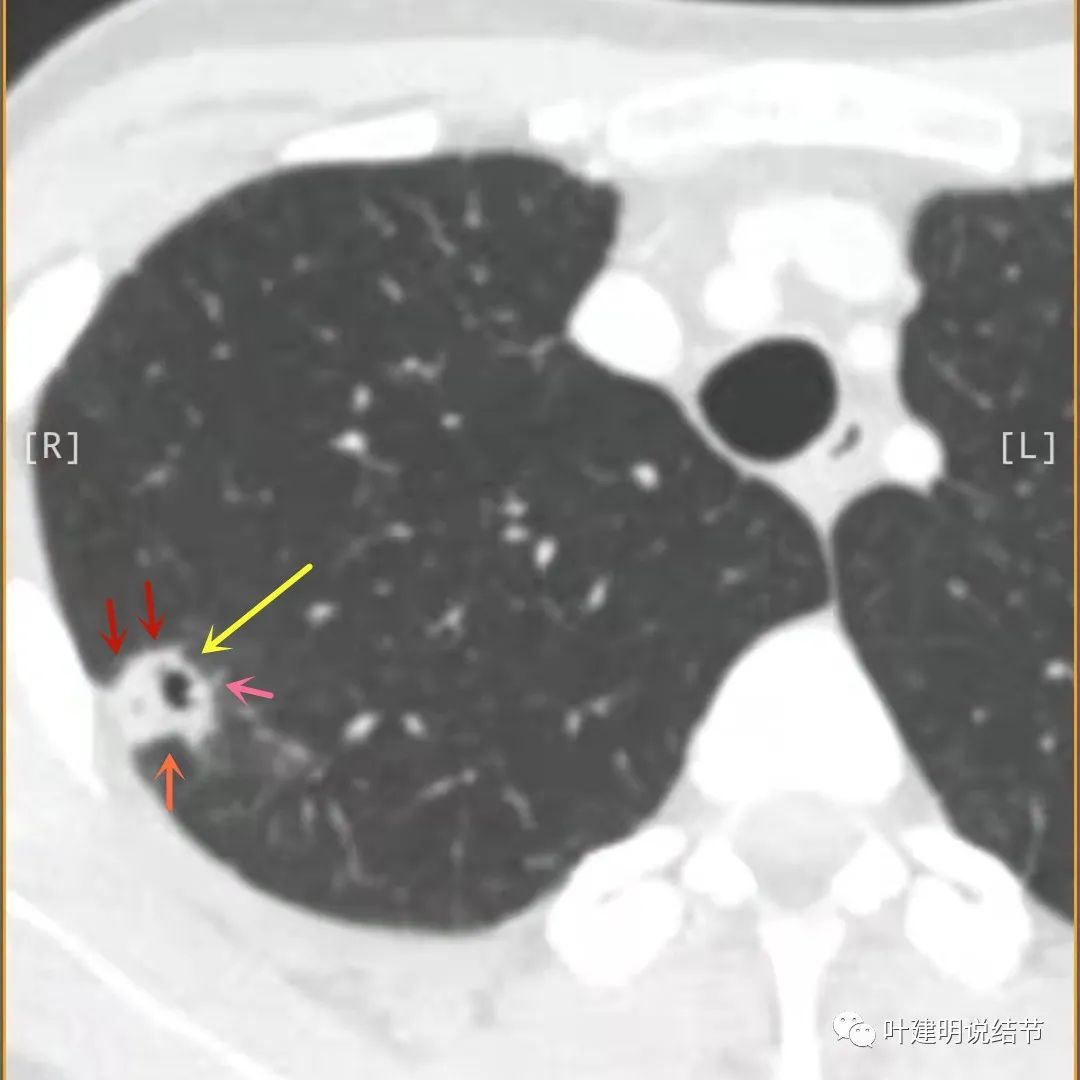

邻近胸膜有增厚(蓝色箭头),主病灶实性部分密度过高(粉色箭头),旁边有磨玻璃影,散且模糊(砖色箭头),病灶有空腔(黄色箭头)

主病灶边界较清(红色箭头),实性部分密度过高(粉色箭头),病灶边缘向内凹,缺乏膨胀性(桔色箭头),病灶有空腔(黄色箭头)

邻近胸膜有增厚(蓝色箭头),主病灶的壁密度过高且整个壁密度都高(粉色箭头),旁边有磨玻璃影,散且模糊(砖色箭头)。内壁不均质(此不舒服)

邻近胸膜有增厚(蓝色箭头),主病灶囊壁密度过高(粉色箭头),内部有突起(细红色箭头),旁边有磨玻璃影,散且模糊(砖色箭头),中间有空腔,内壁有些区域又是光滑的